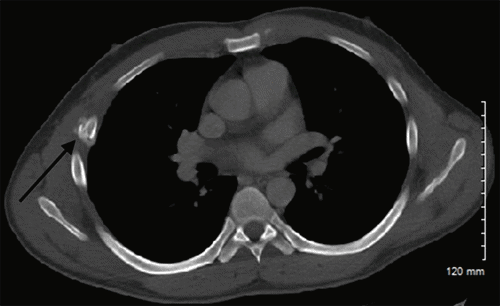

While the patient reported initial relief of symptoms within 48 hours of the initial procedure, he experienced a recurrence of nausea, distension, and abdominal pain. Post paracentesis, CT imaging of the abdomen pelvis failed to show extravasation of oral contrast from viscera (Figure 1) but revealed a contracted gallbladder and re-accumulation of ascites. A hepatobiliary iminodiacetic acid (HIDA) scan showed a biliary leak from the region of the gallbladder fossa (Figure 2). Magnetic resonance cholangiopancreatography showed recurrent ascites but no biliary obstruction (Figure 3). No traumatic injuries were identified on the initial imaging. Repeat paracentesis yielded one liter of bilious fluid, again with a resolution of symptoms.

Figure 2. Hepatobiliary Iminodiacetic Acid Scan with and without Morphine with Evidence of Biliary Leak (circle). Published with Permission

At his postoperative visit a week later, he complained of persistent abdominal and chest wall pain, prompting repeat imaging, which revealed no intraabdominal abnormalities. However, fractures of the right fifth and sixth ribs of indeterminate age were noted, consistent with trauma (Figure 5). On further questioning, the patient admitted to a fall several weeks prior with trauma to his right chest and reiterated he did not recall the events leading to his initial hospitalization at the outside facility. The pain had resolved by the time of his follow-up visit two weeks later. Pathology confirmed gallbladder perforation without cholelithiasis or inflammation.

Ascites and abdominal pain in individuals who abuse alcohol may not always be attributed to cirrhosis. Paracentesis is useful and can start the diagnostic cascade to define rarities like an isolated rupture. HIDA scans are often the best tool for diagnosis. Early operative intervention for Type I perforations directly affects morbidity and mortality.